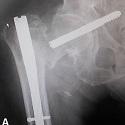

Complication rare du clou gamma: migration de vis cervicale au contact des vaisseaux iliaques

Younes Ouchrif, Issam Elouakili

PAMJ. 2014; 18: 188. Published 04 July 2014